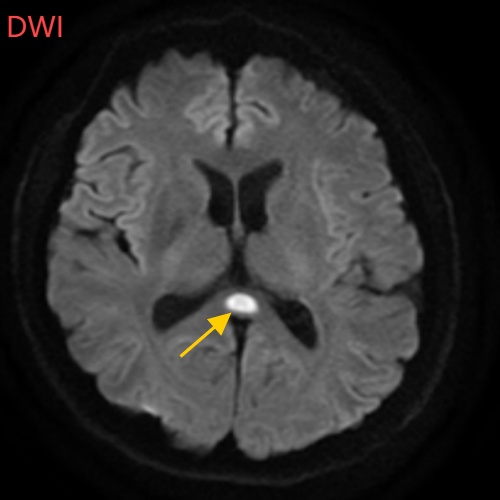

经过头部磁共振平扫、弥散、增强影像等检查

可逆性胼胝体压部综合征

小董的影像结果显示,胼胝体压部发生病变

经过一周治疗,小董的胼胝体压部病变明显好转